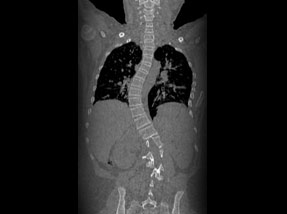

• Post Surgery

• Post SurgeryAfter

Case 1